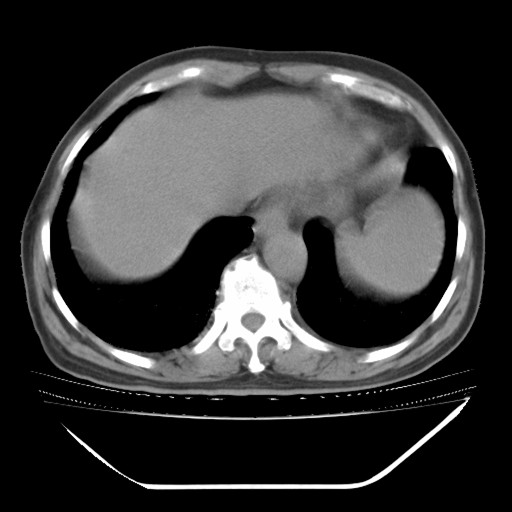

以下是引用hhcckk在2009-5-29 10:34:00的发言:[br]左下肺片絮状边缘模糊影,考虑感染,建议治疗后复查[br]